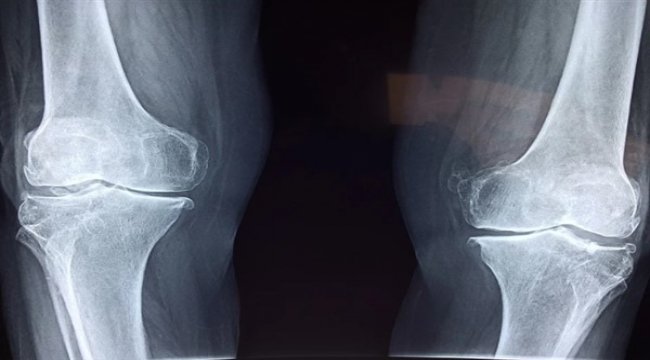

Kalça ekleminde hissedilen ağrıda yapılan özel testlerle hastanın belli hareketleri yapıp yapamadığı incelenir. Kalça filmi kalçanın yapısında bozukluk olduğunu gösteren çok önemli ayrıntıları ortaya koyabilir. Böylelikle tedavisi mümkün olmayan, kişiyi protez ile yaşamaya mahkum bırakan bir hastalık olan kireçlenmeye doğru gidebilecek bir tablo, çok önceden tespit edilerek gerekli önlemler alınabilir.